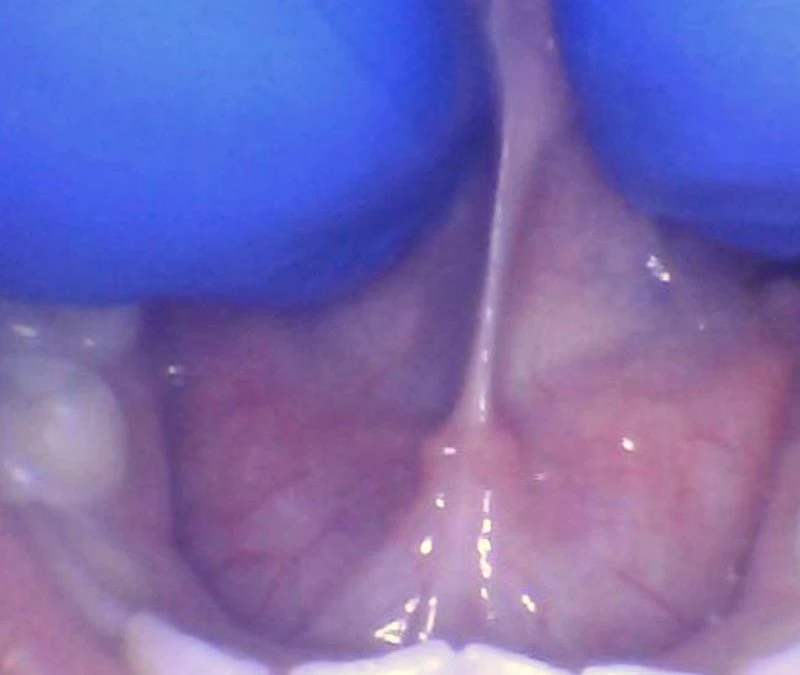

How Do You Check A Child For a Tongue-Tie Properly?

Sep 10, 2020 | Tongue Tie Terminology, Tongue-Tie Tips

Last week we discussed how to check an infant for a tongue-tie. Young children are typically more difficult to check for a tongue-tie, but this age group can often have incredible results if it is released properly and fully, and aftercare exercises and stretches are...